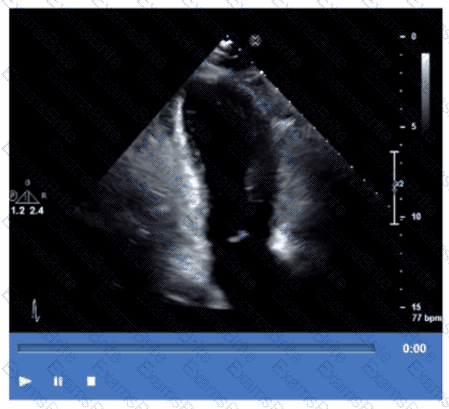

Which mitral regurgitation jet direction is most consistent with hypertrophic obstructive cardiomyopathy?